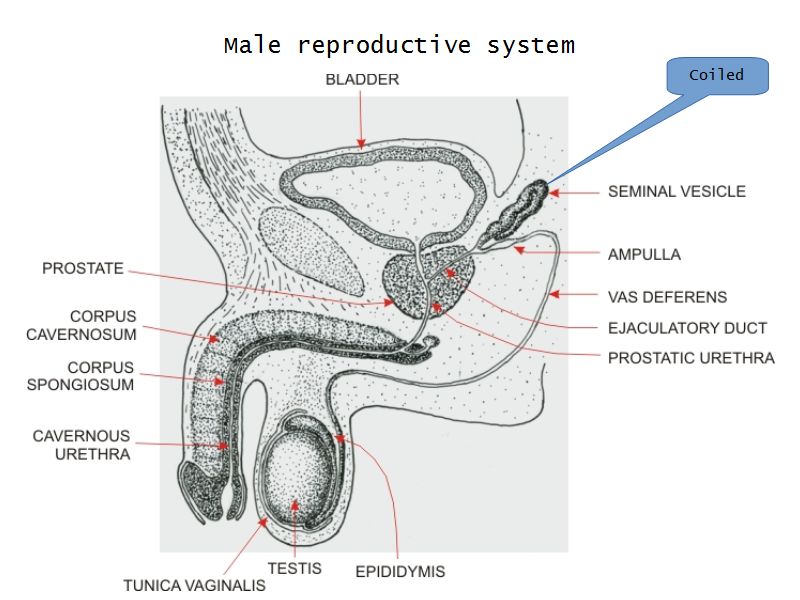

Testis

Slide 84

Testis

- Tunica albuginea

- Lobuli

- Seminiferous tubuli

- Epididymus

- Ductus deferens

Epididymus

Ductus deferens

Also vas deferens

Vesicula seminalis

Slide 81Vesicula seminalis

Prostate

Slide 80Prostate

Penis

Slide 83Penis